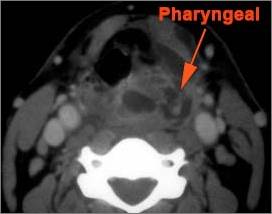

There is excessive enhancement or thickening of the mucosa or hypertrophy of the pharyngeal, palatine or lingual tonsillar tissue or the lymphoid tissue along the glossotonsillar sulci and posterior pharyngeal wall. [Yes/No]

There is an abscess relatively centrally within the lymphoid tissue of the palatine tonsil. [Yes/No]

There is evidence of a developing abscess at the periphery of the lymphoid tissue of the palatine tonsil within the potential peritonsillar space. [Yes/No]